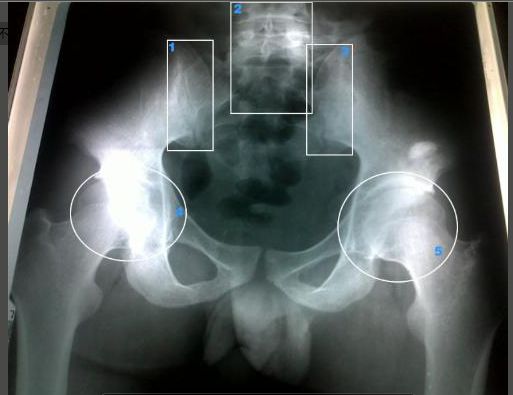

• 强直性脊柱炎具体的检查有哪些